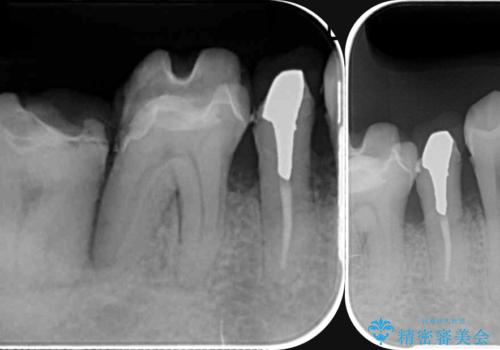

- 歯が全体的に揺れ始め、恐怖を感じ他院に相談に行ったところ、全体的な歯周病の問題・抜歯の必要性・入れ歯の提案を受け、入れ歯以外の選択肢を希望され来院されました。

全体的な歯周病検査を行い、多数の残すことのできない抜歯の必要な歯を認めたため、残せる歯に対しての徹底的な歯周病治療、失った歯に対しブリッジ・インプラント治療を全顎的に行っていくこととしました。